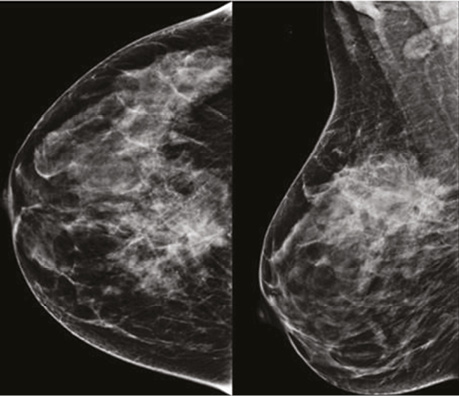

Проаналізувавши надані площинні мамографічні зображення, зазначено високу щільність паренхіми МЗ категорії ACR С з наявністю середньоінтенсивного гетерогенного ущільнення в ретромамарному просторі на 1 год правої МЗ розміром 27×21×22 мм з нечіткими променистими краями. Відзначалася наявність перинодулярної інфільтрації паренхіми, згущення структурного малюнку МЗ навколо вузлового компонента. У правій аксилярній ділянці лімфатичний вузол розміром 32×14 мм, кірково-медулярна диференціація простежується, кірковий шар нерівномірний, потовщений до 5,3 мм (рис. 1).

Рис. 1. Площинна мамографія в R-СС- та R-MLO-проєкціях. На 1 год ретромамарно — гетерогенне середньоінтенсивне вузлове новоутворення з нечіткими краями. У правій пахвовій ділянці лімфатичний вузол з нерівномірно потовщеним кірковим шаром